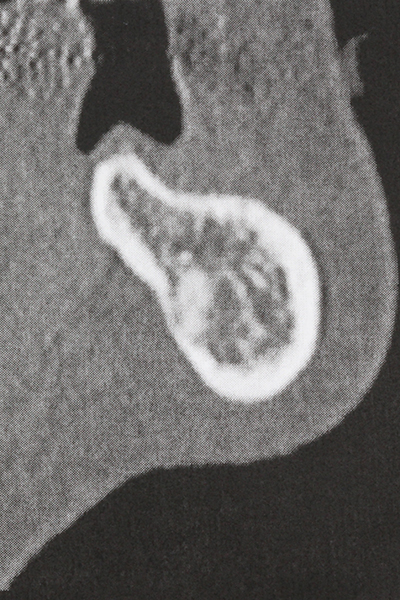

Костната тъкан е не само минерализирана структура, тя съдържа и съществено количество колагенови влакна. Това означава, че тя има не само добра компресивна сила, но и известна степен на гъвкавост, която може да се възприеме като предимство при извършване на костна аугментация. В класическата процедура по разширяване чрез костно разделяне, атрофиралият алвеоларен гребен е разделен надлъжно и внимателно разширен след достигане на подходящата остеотомна дълбочина (Фиг. 13-16), в идеалния случай без допълнително отстраняване на периостеума (Brugnami, Caiazzo et al. 2014, Stricker, Fleiner et al. 2014). Системите с винт и пластини с увеличаване на разстоянието при разширяване са доказали ефективността си при разделяне на двете костни ламели, оставайки под прага на фрактурите. В общи линии, оставащата ширина на костта от поне 3–4 mm е задължителна (Chiapasco, Zaniboni et al. 2006), за да се гарантира добра гъвкавост и достатъчно костно покритие за бъдещото поставяне на импланти. Ако е необходимо, вертикалната остеотомия на едната или двете страни може да подобри гъвкавостта. Комбинацията с допълнителни техники за аугментация, особено в букалната страна, е описана като алтернатива на класическата техника.